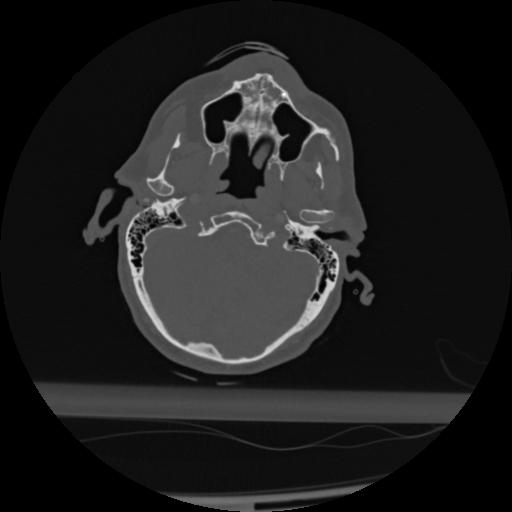

22 ANGIO,CE,Vol,0.5,ANGIO,,